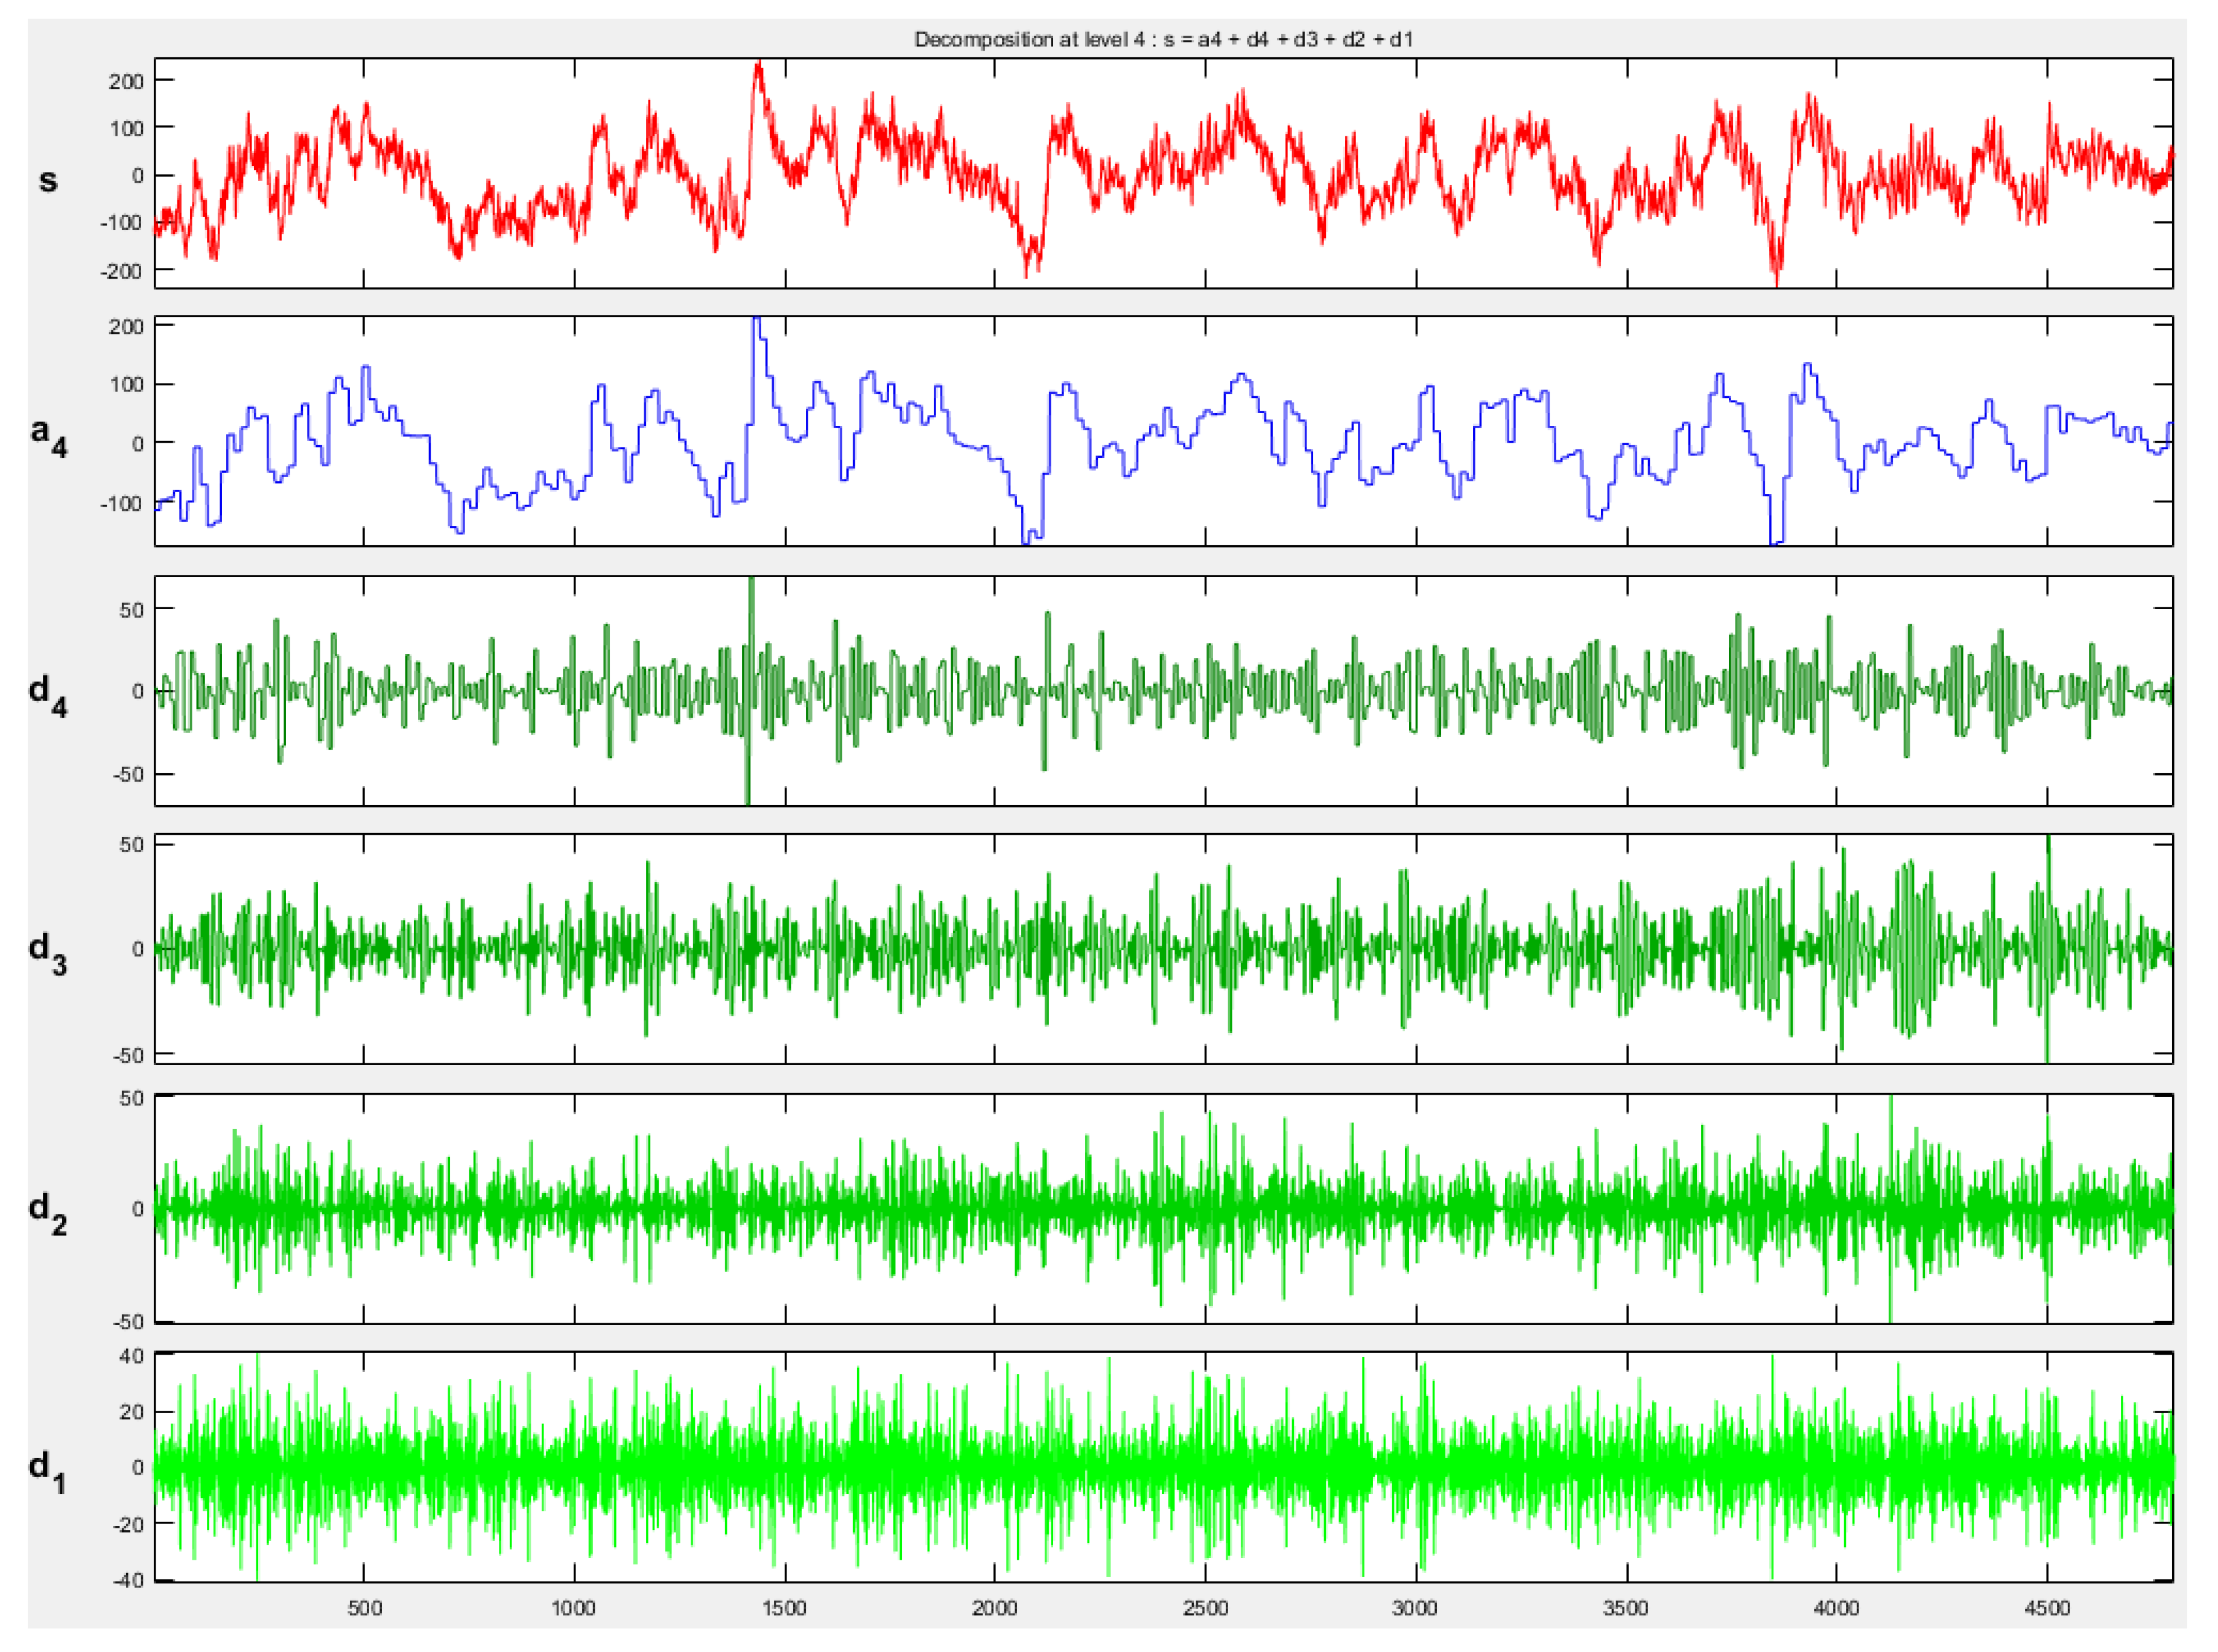

2.4. Wavelet Transform